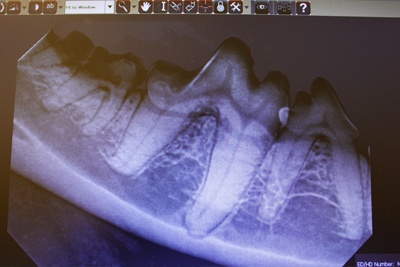

- Complimentary preanesthetic blood work AND full-mouth dental radiographs (grades 2-4)